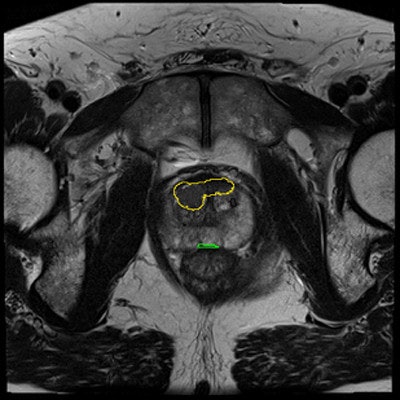

Henkjan Huisman, PhD, assistant professor of radiology at the diagnostic image analysis group at the department of radiology, Radboud University Medical Center.Something better still is needed, and that is prostate cancer CAD. A few years ago PhD student Geert Litjens, Huisman, and colleagues developed a fairly simple but functional prostate cancer CAD that performed "pretty well," Litjens said. The group has since updated it, expanding it to include zonal registration of tumors and multiatlas reference capabilities. There is feature extraction that looks for quality and texture features and a voxel classifier for tumor candidate detection and segmentation as well.

The CAD works in two stages: voxel classification and a subsequent candidate segmentation and classification stage, he noted. CAD features include quantified T2 measures, apparent diffusion coefficient (ADC), pharmacokinetics, texture, and anatomic characteristics. Both receiver operating curve (ROC) and free-response ROC (FROC) were used for analysis.

Prostate CAD scheme shows high detection rate, and results can be improved when CAD is used as a second reader. In 130 prostate cancer patients, CAD and radiologists were shown to have similar sensitivity. Simulating the addition of CAD improved sensitivity from 0.78 to 0.87 (indolent versus aggressive tumors). It improved sensitivity from 93% to 98% at PI-RADS 4.For aggressive cancers at PI-RADS levels four and five, "we able to show that CAD improves the area under the curve from 0.78 to 0.87," Huisman said. "If a radiologist were to use CAD, then the sensitivity would increase 98%, which would really allow them to not do any biopsies for PI-RADS, which is clinically very relevant."